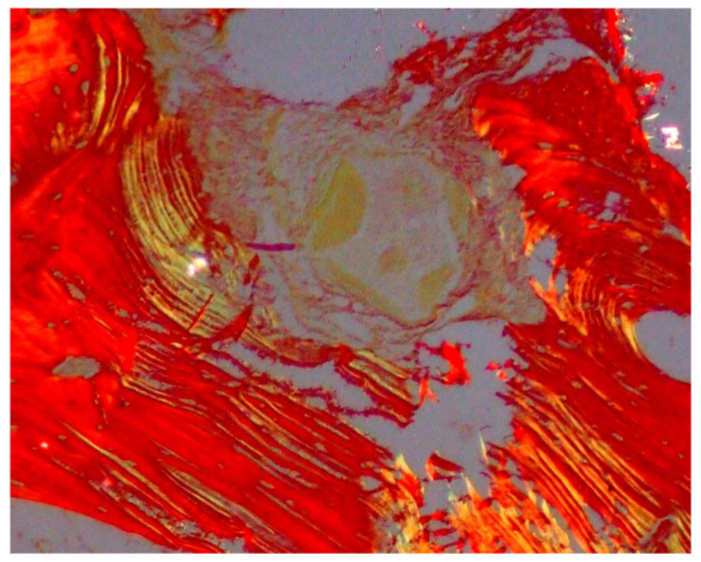

Biopsies were fixed in 10% formalin, decalcified with 0.5M EDTA, and sectioned. Hematoxylin and eosin (HE), Van Geison, Mason trichrome and Picrosirius Red were used. Microscopic analysis revealed remnants of dentin particles integrated with new lamellar bone. Plump osteoblasts, entrapped osteocytes, and fibrovascular stroma with minimal chronic inflammation were evident, confirming osteoconductive and osteoinductive potential. Mature bone trabeculae along with residul graft material were confirmed with various special stains.